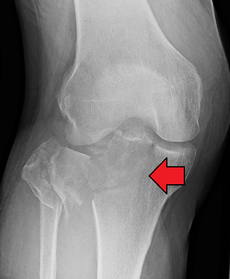

Subtle tibial plateau fracture on an AP X ray of the knee

Lipohemarthrosis due to a tibial plateau fracture- A tibial plateau fracture seen on X-ray